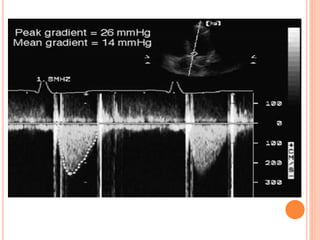

• For example, Doppler imaging can be used to measure

prostheses (Fig.).

DETERMINATION OF GRADIENTS

ACROSS PROSTHETIC VALVES.